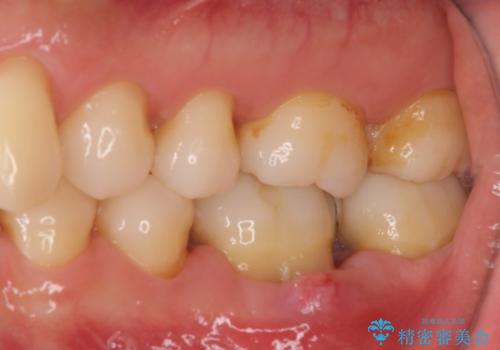

根管治療などを行った後に、オールセラミッククラウンにて補綴することとしました。

根管治療を終えた後には、今まで気になっていた痛みが消え、快適に日常生活を送れるようになりました。

痛みが取れるとともに、気になっていた大きな銀歯も自然なセラミックとなり、患者様には大変満足していただけました。